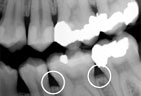

Periodontitis |